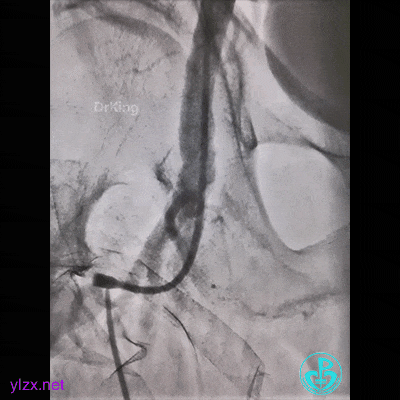

因为是心梗,患者持续胸痛,生命体征不稳,不再尝试,改腿。

然而,还是不能到位。

带的J-W转,突然血压没了,看下面,悲剧了。

患者持续胸痛,先放这里,改入路开通心脏血管!

走左边,终于到位,造影。